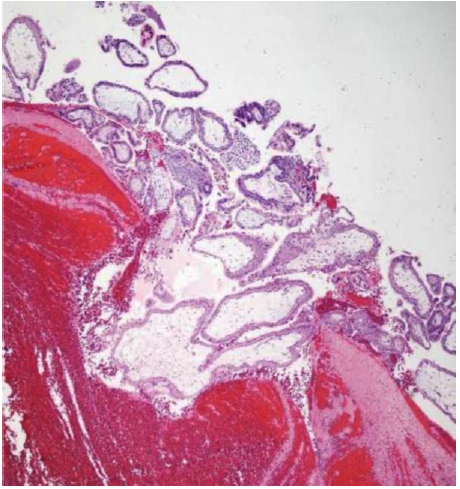

The surface of the mass was intact but minimal oozing at multiple points was seen. A clamp was applied at the base, and the mass was removed. No other sources of intra-abdominal bleeding were identified by the surgical team. Upon sectioning the mass, a fetus approximately 20 weeks of gestational age, with placenta was visualized (Figure 2) and sent for histopathological examination. The weight of fetus was found to be 419 grams. Histopathology report confirmed the diagnosis of tubal ectopic pregnancy (Figure 3).

Figure 3. Histopathological section demonstrating chorionic villi consistent with ectopic pregnancy